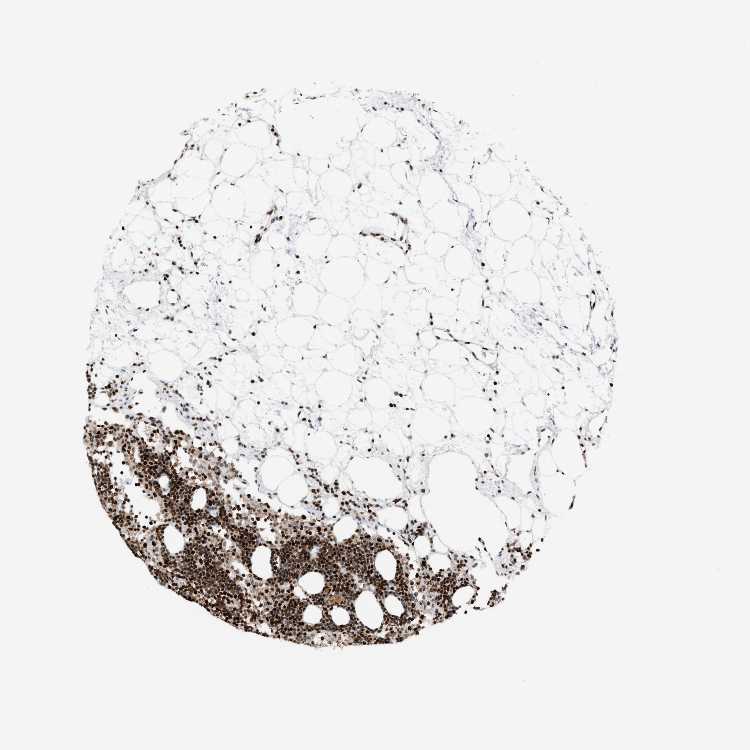

LYMPH NODE - Antibody stainingi

Antibody staining in the annotated cell types in the current human tissue is reported as not detected, low, medium, or high, based on conventional immunohistochemistry profiling in selected tissues. This score is based on the combination of the staining intensity and fraction of stained cells.

Each image is clickable and will lead to virtual microscopy that enables deeper exploration of all samples and also displays staining intensity scores, fraction scores and subcellular localization as well as patient and tissue information for each sample.

Antibody HPA022961Antibody HPA024457

Germinal center cells HighHigh

Non-germinal center cells HighHigh